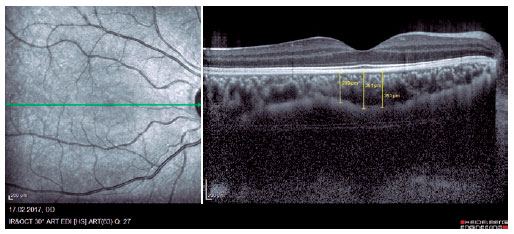

We retrospectively evaluated 32 obese patients with BMI of >30 kg/m2 who presented at the Internal Medicine Polyclinic due to obesity and who were also evaluated at the Ocular Diseases Polyclinic between January 2016 and June 2017 and 45 healthy control individuals. Eye IOP and OPA values of patients measured using Pascal DCT (Ziemer Group, Switzerland) and CT measured using enhanced depth imaging (centralized fovea for choroildal imaging) OCT (85,000 Hz OCT2 Next Generation SPECTRALIS OCT, Heidelberg Engineering) were assessed. These values were measured by the same physician and at the same time of the day. Only the most reliable measurements with scores 1 and 2 were included in the study. CT was manually measured by a single ophthalmologist based on the external boundary of retinal pigment epithelium and that of the choroidal vascular bed. It was measured three times at the subfoveal, nasal, and temporal regions at a distance of 500 µm from the macula, and the average of these three measurements was used for analyses (Figures 1-3). IR was assessed using the homeostasis model assessment-estimated IR (HOMA-IR) index(9), which was calculated as follows: HOMA-IR=[fasting plasma insulin (mIU/mL) × fasting plasma glucose (mmol/L)]/ 22.5(10). HOMA-IR index of 2.5 was set as the cutoff value(11). Patients with ocular tension and corneal disease, those with nonobesity systemic diseases, those who underwent eye surgery, and those who underwent interventions such as laser therapy and intravitreal injections were excluded from the study. This study was approved by the Ethics Committee of the Adiyaman University (#2017/7-19).